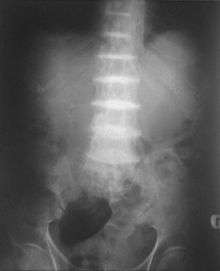

After the age of thirty people begin to develop pain in the weight-bearing joints of the spine, hips and knees. The pain can be severe to the point that interferes with activities of daily living and may affect ability to work. Joint replacement surgery (hip and shoulder) is often necessary at a relatively young age.[1] In the longer term, the involvement of the spinal joints leads to reduced movement of the rib cage and can affect breathing.[1] Bone mineral density may be affected, increasing the risk of bone fractures, and rupture of tendons and muscles may occur.[1]

- List of radiographic findings associated with cutaneous conditions